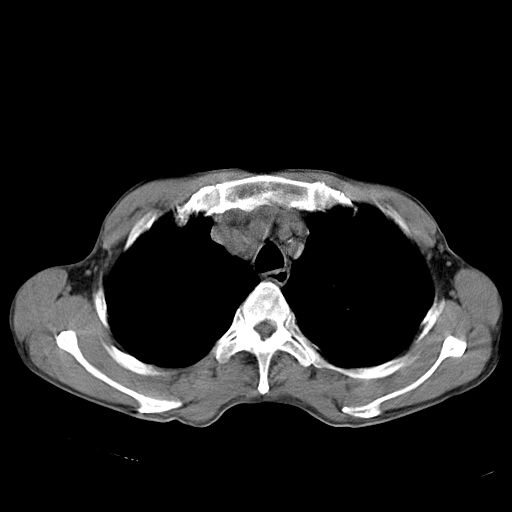

以下是引用苯小孩在2007-5-24 12:47:00的发言:[br]右侧肺门处不均匀密度软组织块影,远端肺组织见斑片模糊影,纵隔内淋巴结明显肿大,边界不清.<纵隔窗第12层面支气管内似见软组织结节>[br]考虑:1、右侧中央性肺癌并阻塞性肺炎并纵隔淋巴结转移可能性大.建议强化或纤支镜进一步检查.[br]2、隆突下淋巴结肿大/食道病变?请做鉴别检查.

以下是引用zhangzhongshou在2007-5-24 12:55:00的发言:[br]1、右肺中叶中心型肺癌并右肺门、隆突下、纵隔淋巴结转移。右肺中叶阻塞性肺炎。

以下是引用jw-830在2007-5-24 15:24:00的发言:[br][br] [br] 考虑右肺中央型肺癌并阻塞性炎症,右肺门及纵隔淋巴结转移。 [br] [br][br]